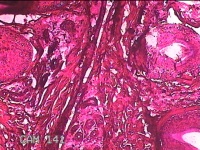

头部肿物

性别

男

年龄

18岁

临床诊断

头部局部肿物

一般病史

发现头顶部外凸结节半年余,近日出现局部破溃。

标本名称

大体所见

灰白暗红色肿物1.5x0.8x0.3cm一个,表面糜烂,结节表面有少许毛发,切开结节呈实性,切面灰白粉红色,质软。

图2